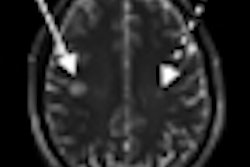

A new study published online February 20 in Archives of Neurology suggests that 7-tesla MRI with a specialized protocol is highly sensitive for detecting plaques in white and gray brain matter in patients with multiple sclerosis (MS).

German researchers used 7-tesla MRI with a T1-weighted magnetization-prepared rapid acquisition and multiple gradient-echo (MP-RAGE) technique. They found that the protocol "clearly delineated every cortical lesion" that was visualized by any other MRI sequence at 1.5 or 7 tesla. The lead author of the study was Tim Sinnecker, from the NeuroCure Clinical Research Center at Charité Medical University in Berlin.

The analysis found that 7-tesla MP RAGE detected a total of 728 lesions, compared with 584 lesions with 7-tesla FLASH and 399 lesions with 1.5-tesla MP RAGE.

Cortical pathology was visible in 10 patients, with the detection of six cortical lesions and 37 leukocortical lesions. Within the 7-tesla acquisitions, each lesion detected at T2-weighted sequences was also visible on corresponding MP-RAGE sequences in the side-by-side analysis. At 1.5-tesla MRI, the MP-RAGE images found only 452 of 561 lesions (80%) in T2-weighted sequences.

T1-weighted MP RAGE at 7 tesla is "highly sensitive" in detecting multiple sclerosis plaques within white and gray brain matter, and the technique depicted structural damage in each lesion, Sinnecker and colleagues concluded.